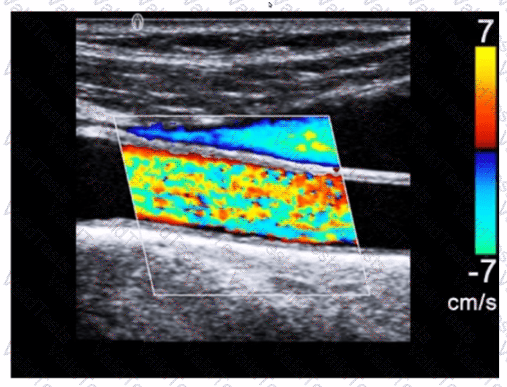

What adjustment is needed to optimize the color in the image below?

Question # 3

Options:

A.

Decrease gain

B.

Increase wall filter

C.

Decrease persistence

D.

Increase pulse repetition frequency